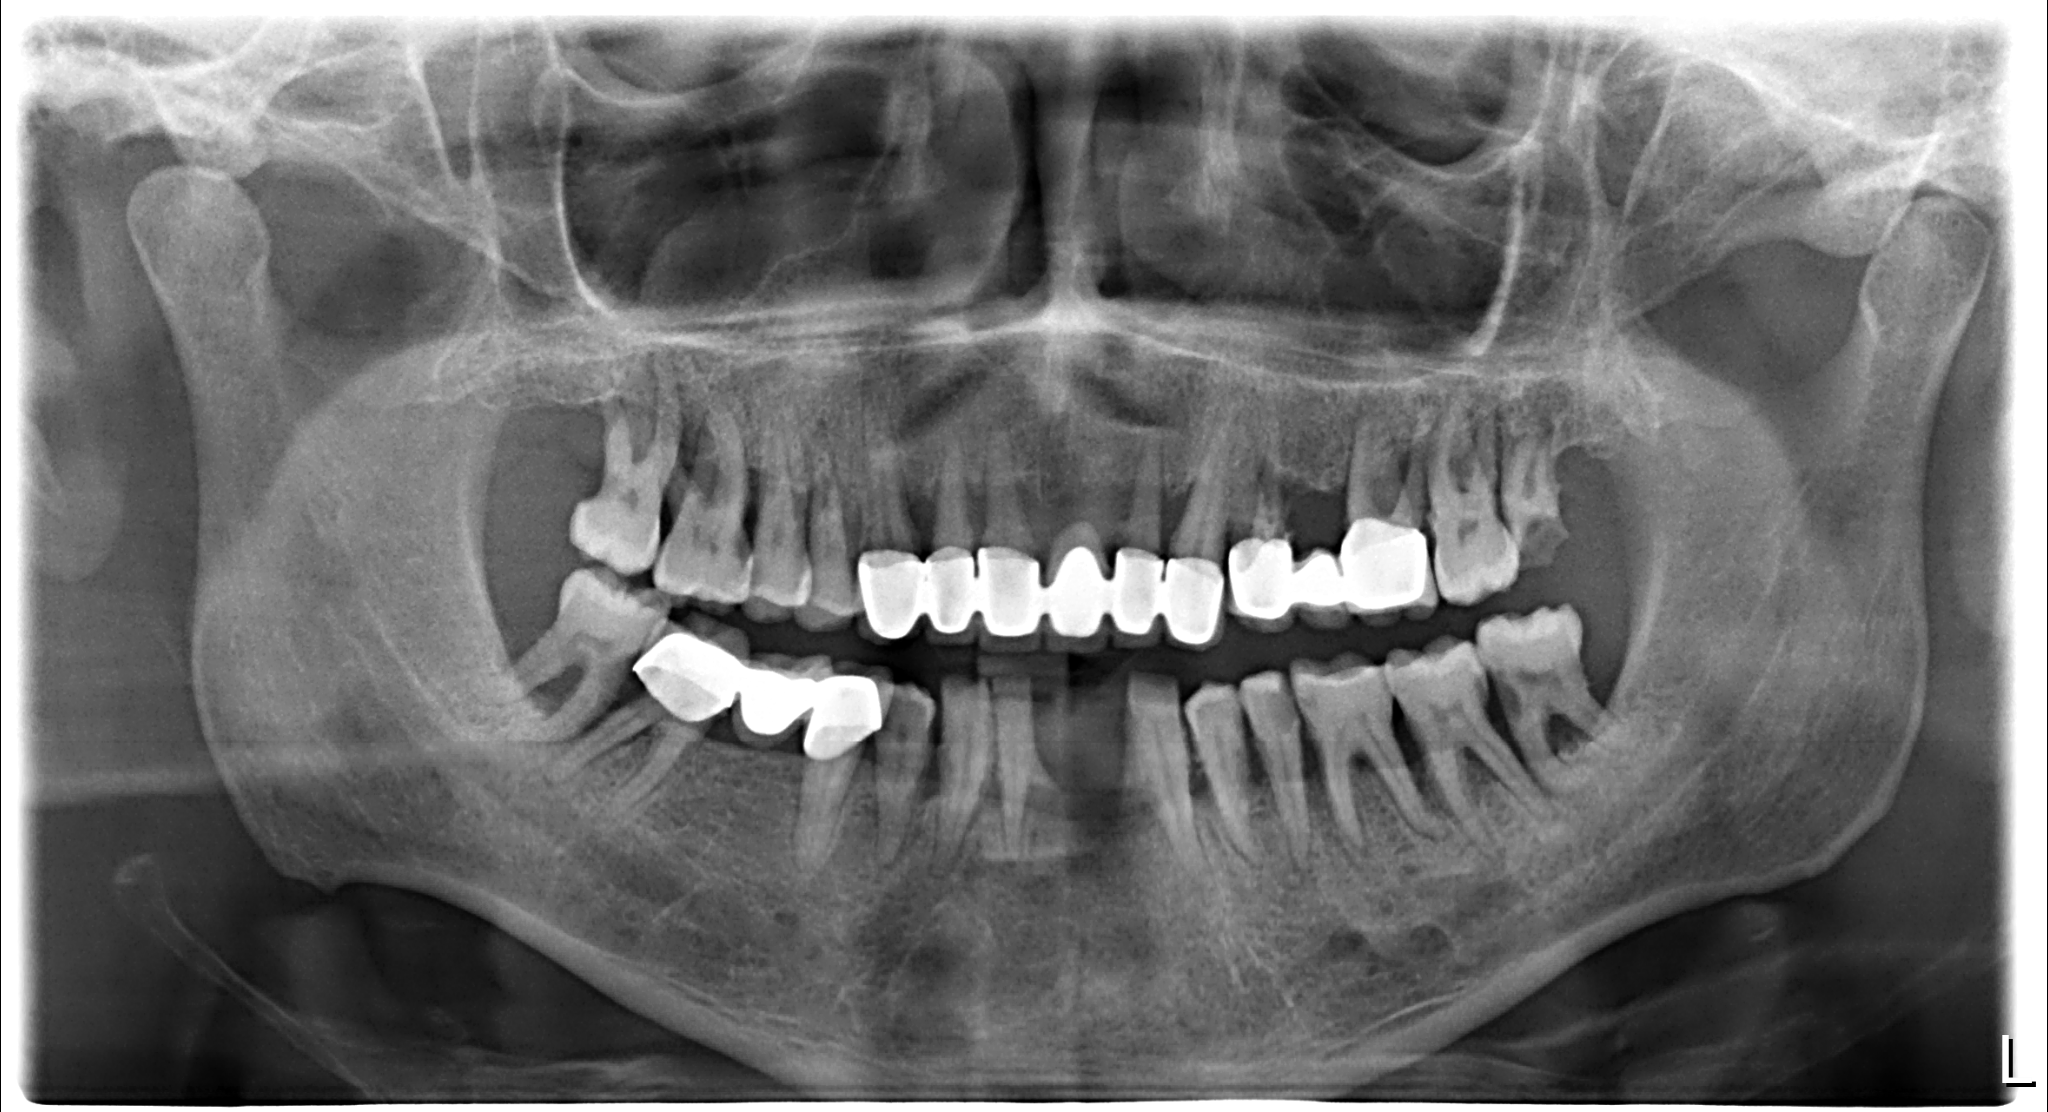

A 46-year-old male patient with severe diabetes mellitus experienced multiple tooth loss in both the upper and lower jaws. The patient also exhibited periodontal problems. Considering the patient's specific conditions, Naxis implants were chosen. Naxis implants are designed to provide better implant stability and success rates, especially in critical cases.

Six Naxis implants were successfully placed in the lower jaw, while eight were placed in the upper jaw. Following implant surgery, immediate healing abutments were used to expedite recovery and reduce the risk of infection.